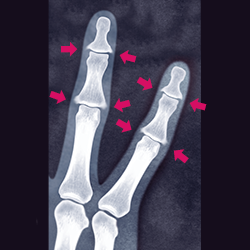

20代で指の骨が破壊される「乾癬性関節炎」、新薬アプレミラストの効果は?MEDLEYニュース。

肌がガサガサ、指も曲がる乾癬性関節炎に「幻の薬」トルツの効果は?MEDLEYニュース。

ヘバーデン結節に似た病気 乾癬による手指の関節炎倉石整形外科クリニック 長野市若穂 リハビリテーション科。